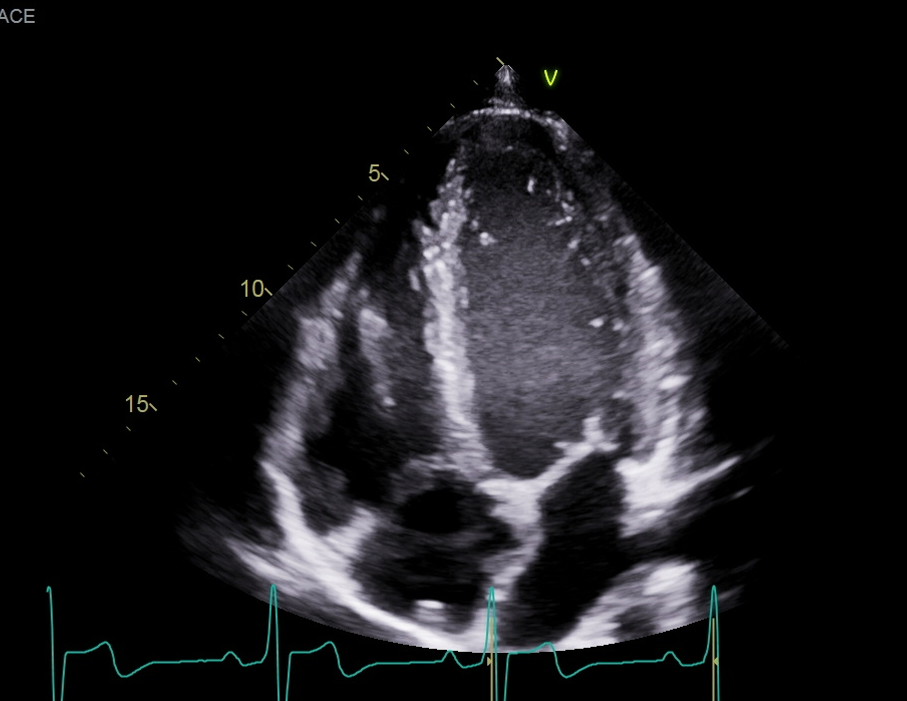

what measure measurement is this, explain how would want to measure this and what View,

Measured the LA area and length in A4C, at its largest dimension before the leaflet tips (MV) open at end-systole, want to exclude the Pulmonary vein and mitral annulus, this is when you need to trace the chamber and length. the normal LA area is going to be less than or equal to 20 or 24? (THIS IS NOT OUT LAV INDEX)